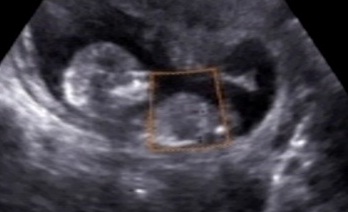

Hi! anyone wants to guess for me? Baby measured about 14 weeks and the tec guessed boy. I couldnt find any clear nub shot in the video. I see something between the legs but since im not an expert I dont know what to think:)

I *think* I see a boy nub in the first picture, obscured by the orange box?

I think it looks really boy. Now, why would a tech draw an orange box with a line going right over the possible nub? Geez!!